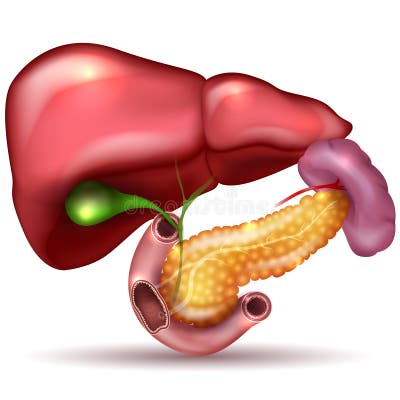

Картинки с надписью Liver: Как выбрать и использовать